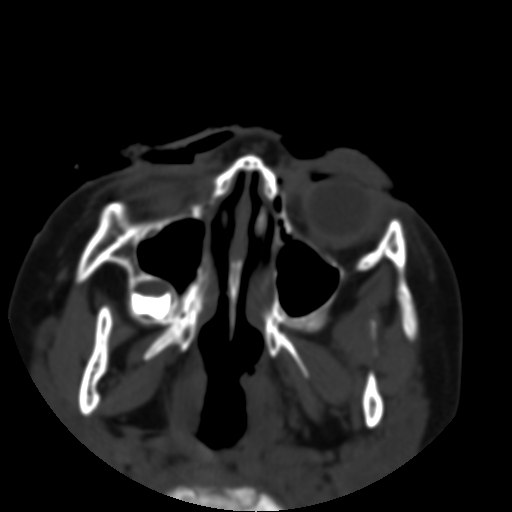

以下是引用深泽交通医院在2009-10-16 8:25:00的发言:[br]右眼环出血伴异物

以下是引用卜一在2009-10-16 15:01:00的发言:[br]右眼球挫裂伤伴异物!

以下是引用拾荒者在2009-10-17 18:38:00的发言:[br]鼻面部皮下积气,右侧睑缘及眼球壁高密度异物影,左侧眼球壁晶状体内侧缘处是圆形低密度影。低密度异物?应提请眼科医生注意。